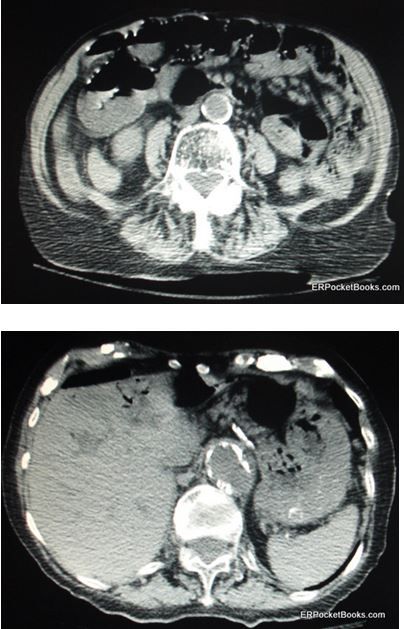

Figures at right show cuts from her CT scan of the abdomen and pelvis.

Answer: Ischemic colitis with perforation

The CT scan of the abdomen showed evidence of severe ischemic colitis involving the transverse and descending colon with pneumatosis intestinalis. There is a small amount of free air from perforation which appears black at the upper part of the Figures. There is also portal venous gas, the black-appearing air within the liver from gas draining out of the colon into the liver. Finally, the aorta appears calcific and somewhat enlarged but without evidence of leakage.